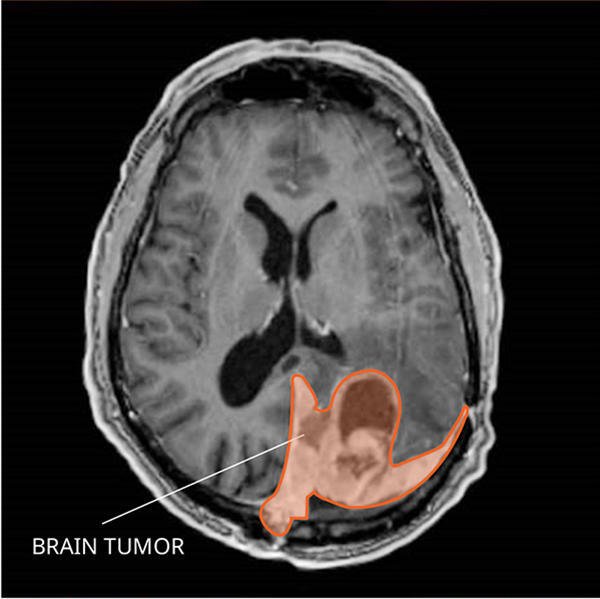

Imaging tests

Imaging tests, such as magnetic resonance imaging (MRI) and computed tomography (CT) scans, play a crucial role in diagnosing brain tumors. These tests provide detailed images of the brain and can help identify the presence, location, and characteristics of a tumor. Imaging tests are usually performed alongside a thorough medical evaluation to determine the most appropriate course of treatment.